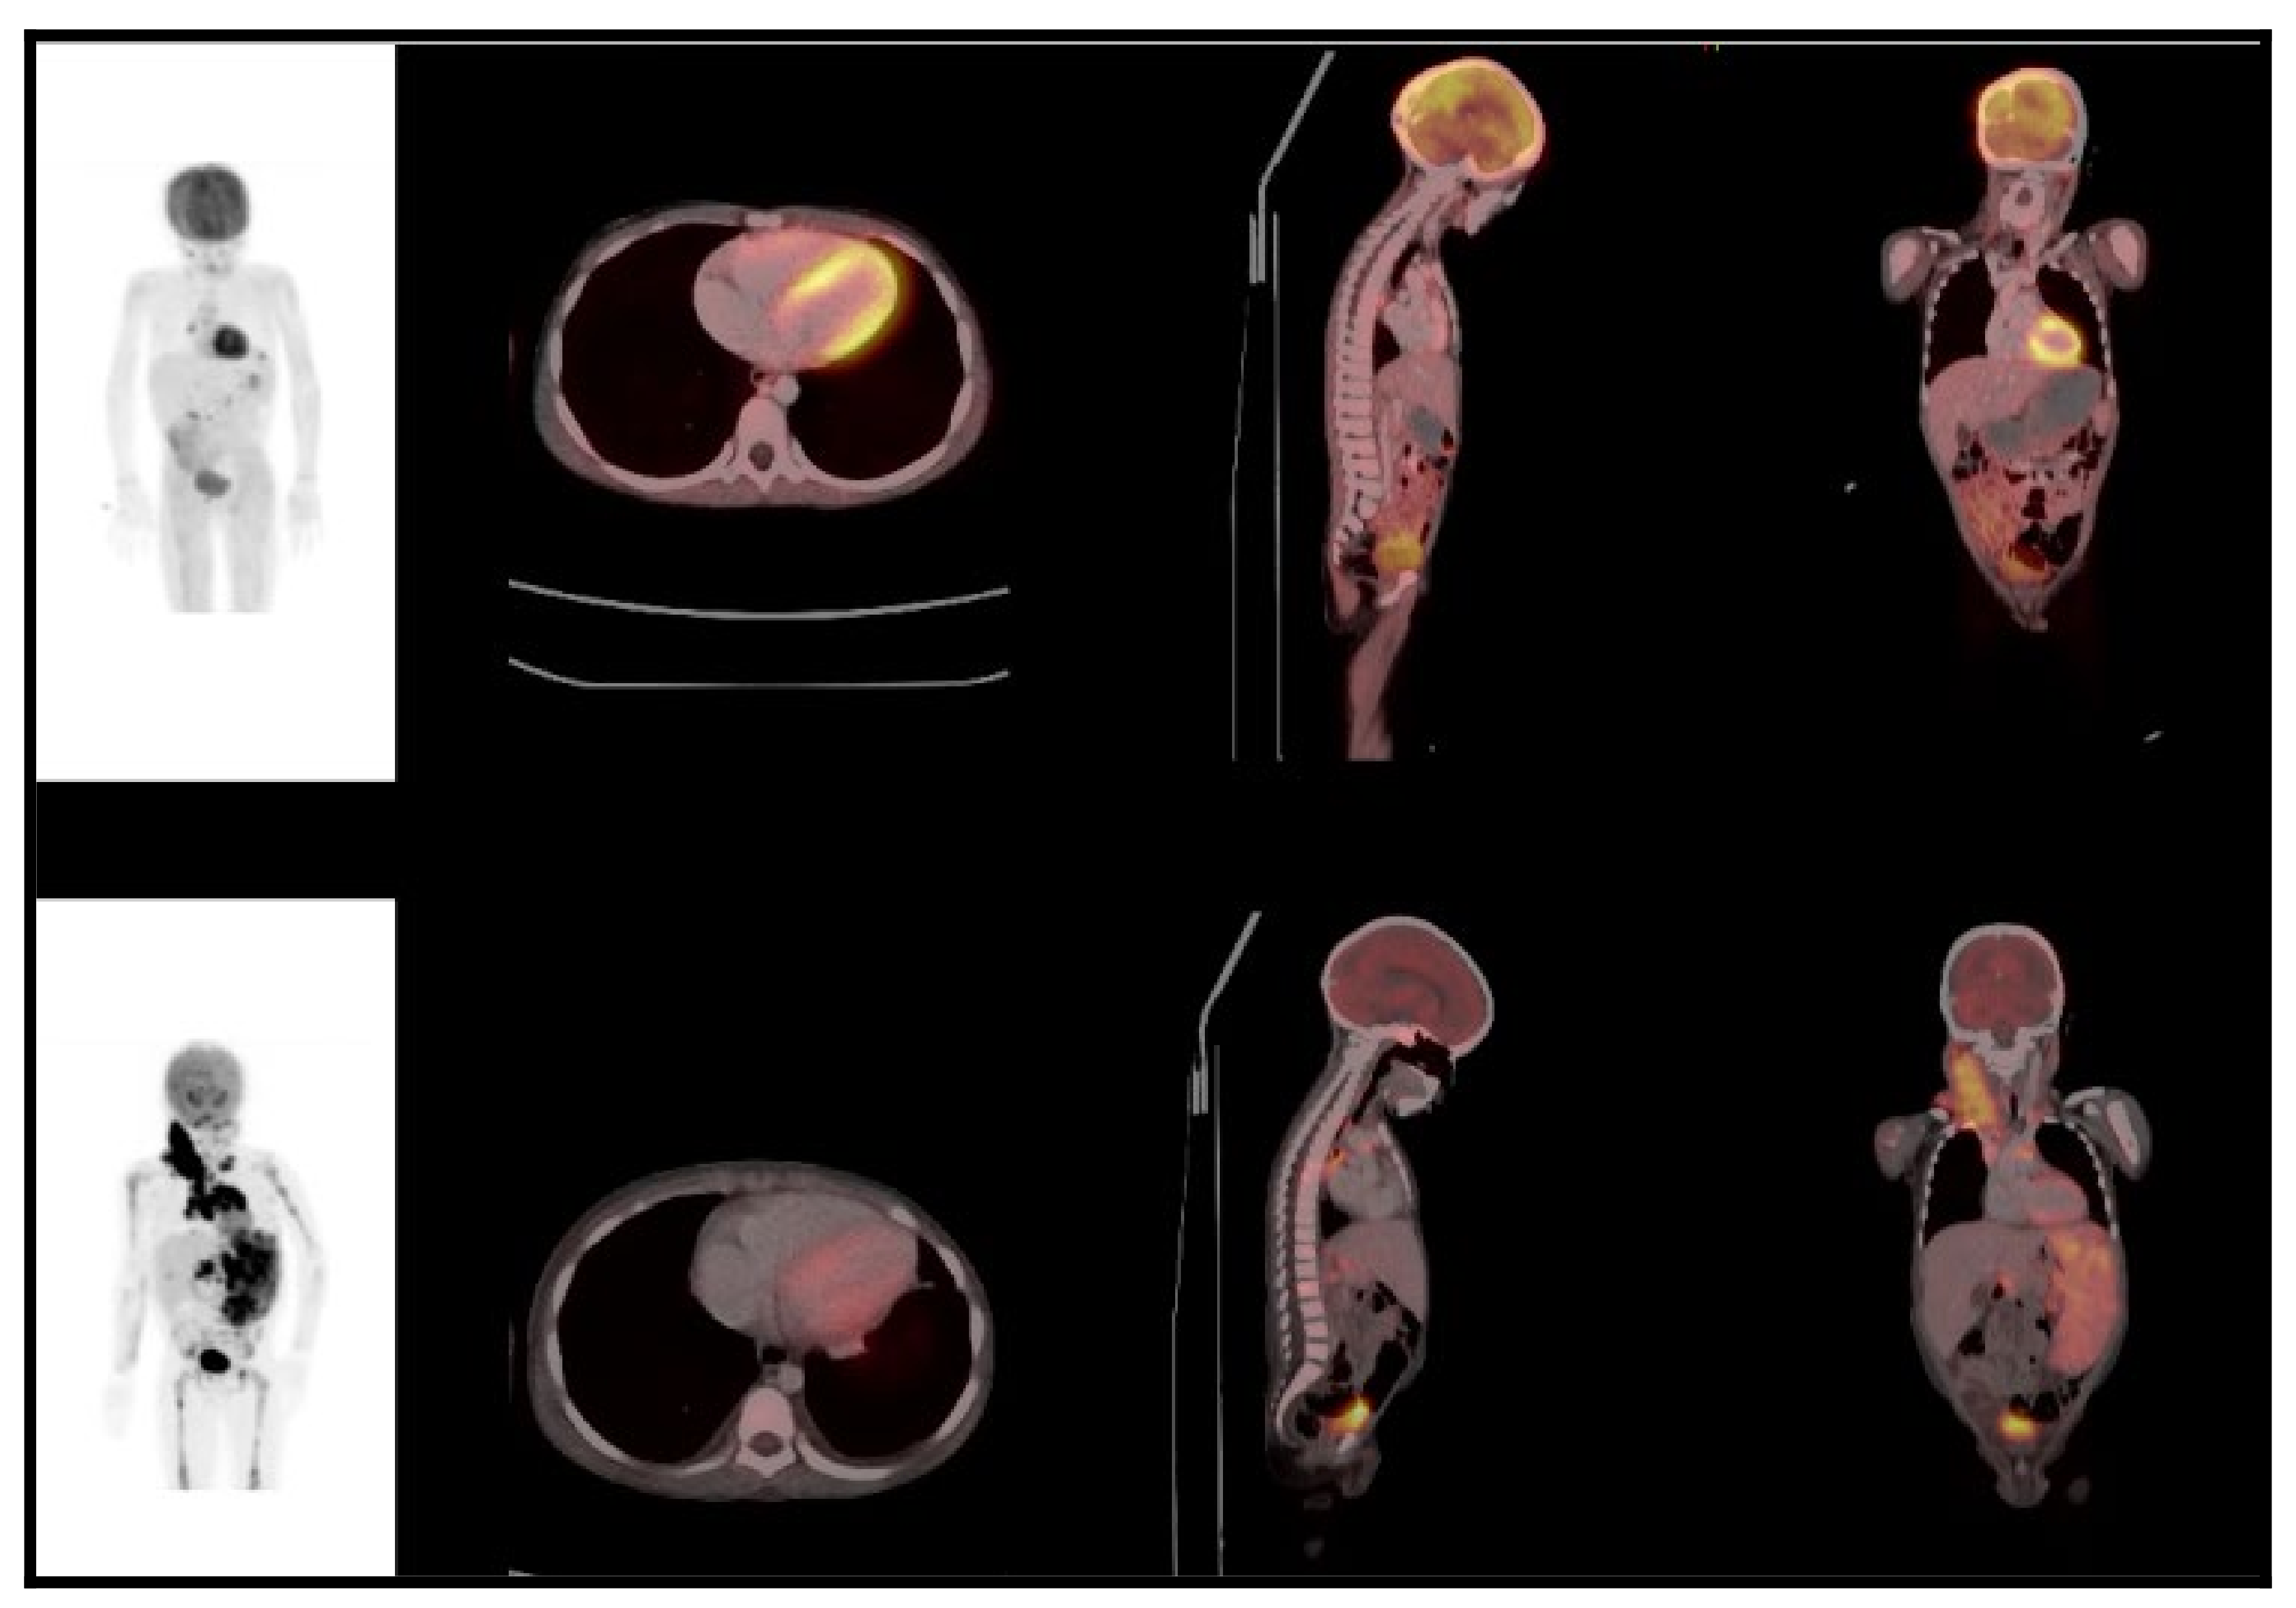

Figure 3.

A 6-year-old male with Hodgkin lymphoma. Baseline images (bottom row: maximum intensity projection, MIP; axial, coronal, and sagittal fused PET/CT) demonstrated splenic and bone marrow involvement, as well as a pericardial effusion and small bilateral pleural effusions. tMTV-901.83 cm3; TLG-3655.06; SUVmax 10.78. After 6 cycles of ABVD (adriamycin, bleomycin, vinblastine, dacarbazine) chemotherapy, a partial metabolic response was noted on the end of treatment PET/CT (top tow). The patient later progressed with a PFS of 11.2 months.